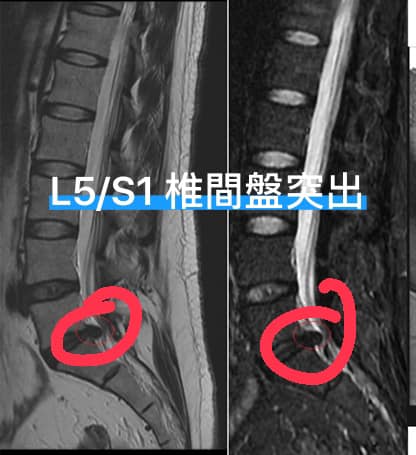

Cervical Spine Treatment Cases 腰椎治療案例 #曾經大痛到送台大急診連打兩支止痛針#椎間盤突出痛到完全無法工作#訪六週密集治療... 2020.09.26 好到症狀完全消失!差點淚灑診間。 2020.09.25 #感謝花蓮鄉親林大姐熱情見證 #腰椎滑脫合併椎管狹窄的病痛 #原本都想去當地開刀了 #... 2020.09.22 #破紀錄了96歲老太爺從新竹北上就醫 #腰椎滑脫合併骨質疏鬆 #原本應該開刀手術但心臟... 2020.09.08 #感謝泰山張阿姨熱情見證 #腰椎滑脫合併椎管狹窄 #原本預定八月中動刀 #逆轉勝成真 #... 2020.09.17 #今天來聊巨大骨刺為何可以吸收回去! #椎間盤突出需要多久才能吸收呢? #馬尾神經症候... 2020.09.08 #典型假性坐骨神經痛 #原來是梨狀肌症候群 #核磁共振排除椎間盤突出 #抽絲剝繭真相大... 2020.08.13 #嚴重椎管狹窄醫案 #感謝台北林大哥熱情見證 #從寸步難行到輕快漫步 #鍛鍊多裂肌的重... 2020.08.12 #椎間盤突出可以吸收回去嗎 #微針治療原理是什麼 #何時一定要接受神外開刀 #一張圖秒... 2020.08.11 #感謝花蓮鄉親林大姐熱情見證 #一分鐘認識椎管狹窄 #原本痛到無法走路打算開刀了 #脊... 2020.08.01 #感謝新莊區林先生熱情見證 #椎間盤突出跟纖維環裂隙的關係 #纖維環破裂突出可以不... 2020.07.28 #逆轉勝又一發case #原本疼痛一年多想說一定要手術治療了 #八週治療後症狀全部消失 #... 2020.07.25 #巨大椎間盤突出一定要開刀嗎 #除了開刀以外的選擇 #感謝台北市吳先生熱情見證 2020.07.24 #腰椎滑脫的疼痛心酸誰人知啊 #一分鐘瞭解腰椎滑脫 #哪一種情況需要積極開刀 #要如何... 2020.07.21 #巨大椎間盤脫垂一定要開刀嗎? #感謝新店林先生熱情見證受訪 #西醫手術有那些選擇... 2020.07.02 ← 上一頁 9 10 11 12 13 下一頁 →